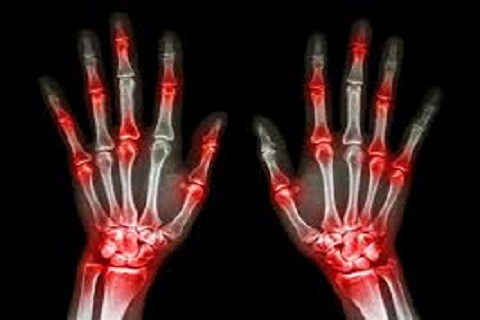

Artrosis

La artrosis es una enfermedad reumática crónica que lesiona el cartílago articular. Se produce fundamentalmente en las manos, las rodillas, la cadera y la columna cervical y lumbar..